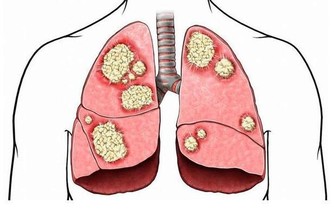

一方面,不吃早餐容易引起身體低血糖,而大腦活動能量主要源於血糖供應,一旦能量供應不上,輕者工作效率降低,重者頭昏甚至暈倒。另一方面,晚上睡覺時胃也會持續分泌胃酸,如果早上不吃飯,胃裡沒有食物中和而呈持續高酸狀態,時間長了就會引起慢性胃病。此外不吃早餐也容易造成膽結石或引發腸道息肉。因此,千萬不要不吃早餐,並且早餐也注意要保證營養。